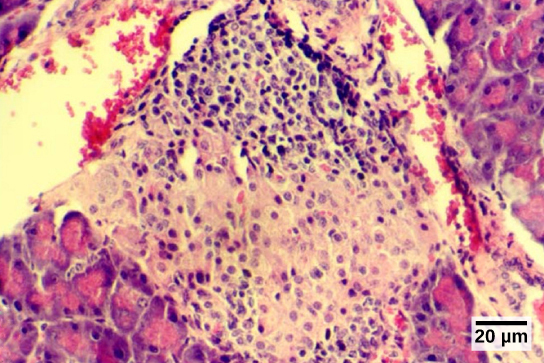

The endocrine cells of the pancreas form clusters called pancreatic islets or the islets of Langerhans, as visible in the micrograph shown in Figure. The pancreatic islets contain two primary cell types: alpha cells, which produce the hormone glucagon, and beta cells, which produce the hormone insulin. These hormones regulate blood glucose levels. As blood glucose levels decline, alpha cells release glucagon to raise the blood glucose levels by increasing rates of glycogen breakdown and glucose release by the liver. When blood glucose levels rise, such as after a meal, beta cells release insulin to lower blood glucose levels by increasing the rate of glucose uptake in most body cells, and by increasing glycogen synthesis in skeletal muscles and the liver. Together, glucagon and insulin regulate blood glucose levels.

The pancreas lies in the abdomen between the stomach and the small intestine. Clusters of endocrine cells in the pancreas form the islets of Langerhans, which are composed of alpha cells that release glucagon and beta cells that release insulin.